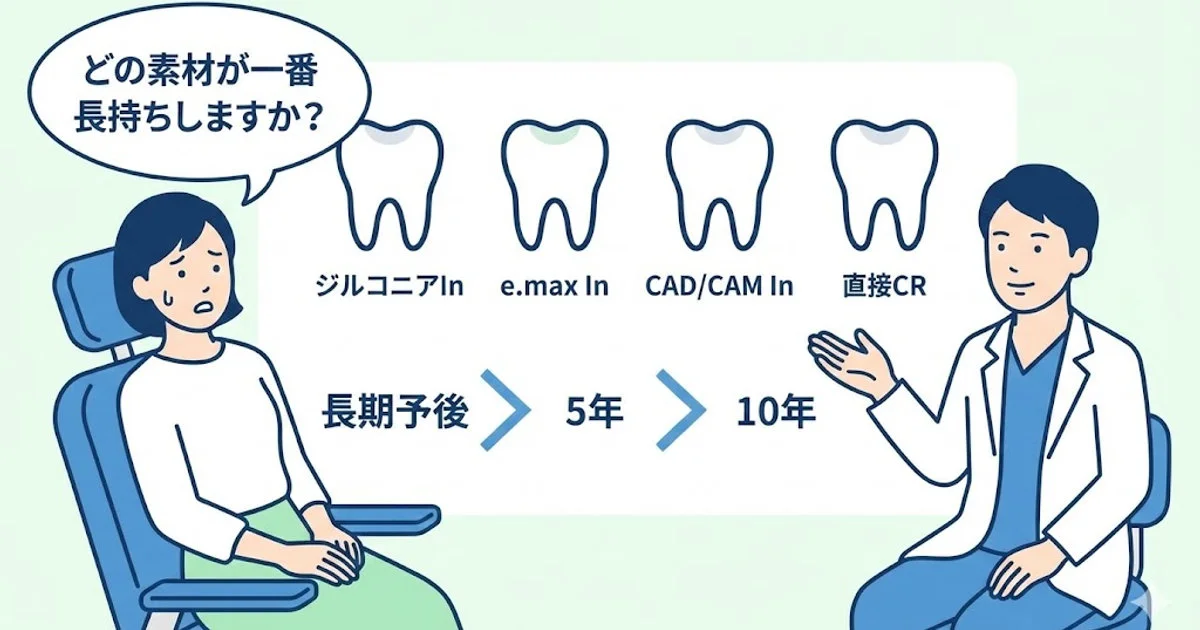

【歯科医師向け】アジア人の奥歯むし歯治療でどの素材が長持ちしやすいか?|臼歯部修復の材料選択と長期予後の考え方

奥歯のむし歯治療で「どの素材が一番長持ちしますか?」と聞かれることは少なくありません。このコラムでは、ジルコニアインレー・e.maxインレー・CAD/CAMハイブリッドレジンインレー・直接コンポジットレジン修復について、アジア人を含む臨床研…